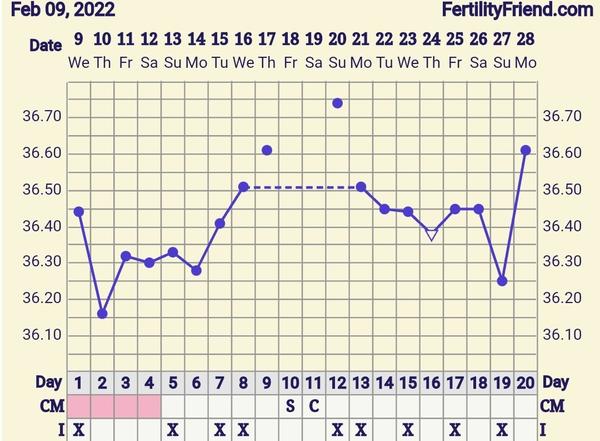

@malarybka3 ja som nemala nikdy 37, pripajam moj víťazný graf, len pre príklad,že aj pri nízkych teplotách môže byť všetko ok, LF som mala 12 dni

@malarybka3 záleží akú máš teplotu predtým. Moja predovulacna bola 36,25 a teraz mam 36,61. Veľmi ojedinele som mala cez 37. Takze záleží ako mávaš telesnú teplotu aj pred aj po. Niekto má predovulacnu to, čo ja poovulacnu. Je to individuálne 😊